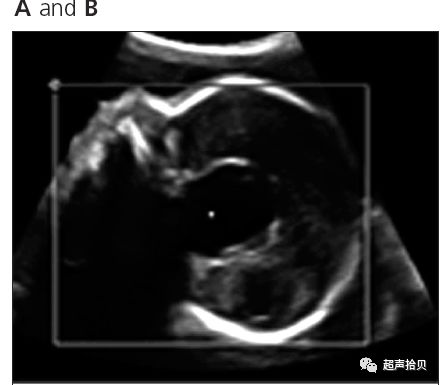

图1:横向声像图显示位于中线蛛网膜囊肿(C), 彩色多普勒没有血流显示;

图1A,妊娠24周后胎儿的矢状面,中线囊肿直径25毫米。 B,胎儿的横断平面脑室扩大,中线囊肿。

一周后,进行第二次扫描以评估进展性结果。 囊状结构和侧脑室分别扩大到28×25毫米和13毫米大小。 矢状位图显示脑干向后位移,阻塞脑室循环(图2,A和B)。 胼胝体正常发育,血流正常,无颅内压增高(图2C)。 三维超声显示孤立的圆形囊状结构(图3)。 使用产前超声检查结果进行胎儿MRI并确认鞍上位置(图4)。 怀疑是蛛网膜囊肿,囊肿和蛛网膜下腔之间可能存在解剖联系的球阀机制被认为是囊肿扩大的原因;